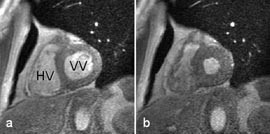

MR kan bidra til å skille mellom idiopatisk dilatert kardiomyopati og ventrikkeldilatasjon pga. kronisk iskemi. Ved førstnevnte tilstand er venstre ventrikkels veggtykkelse vanligvis jevn og normal, men ved dilatasjon pga. kronisk iskemi finner man som regel områder med ekstremt fortynnet vegg etter tidligere infarkter. Hypertrofisk kardiomyopati er vanligvis en ekkokardiografisk diagnose, men MR vil bedre kunne vise den nøyaktige utbredelse av veggfortykkelsen (17) (fig 7). Muskelmassen i høyre og venstre ventrikkel kan beregnes, og cine-MR vil kunne gradere en eventuell mitralinsuffisiens (som er hyppig assosiert med denne tilstanden) og dessuten kunne påvise en unormal diastolisk fylling av høyre ventrikkel (18). Ved restriktiv kardiomyopati vil MRs viktigste bidrag være å utelukke konstriktiv perikarditt; ved førstnevnte tilstand er perikard normal, ved sistnevnte fortykket (minst 4 mm).

T1-vektede MR-bilder viser det normale perikard som en mørk stripe mellom to lyse vev, det epikardiale fettvev og det perikardiale fettvev (fig 8, 9). Fortykkelse av perikard ( ≥ 4 mm) kan av og til sees ved akutt perikarditt, men er mer vanlig ved kronisk perikarditt. MR er en sensitiv metode til å påvise konstriktiv perikarditt (20). I tillegg til perikardfortykkelsen, sees dilatasjon av høyre atrium, v. cava inferior og levervenene og normalt stor eller liten høyre ventrikkel. MR er imidlertid en dårlig metode til å påvise forkalkninger i perikard. Perikardvæske har et varierende utseende ved MR avhengig av innhold av protein og andre makromolekyler. Stormolekylære stoffer forkorter væskens T1 og forårsaker økt signalstyrke på T1-vektede bilder. Eksudatet i perikard ved den sterkt inflammatoriske uremiske perikarditt gir således et moderat kraftig signal på T1-vektede bilder, mens det perikardiale transsudat som sees ved f.eks. hjertesvikt, har nesten manglende signal på T1-vektede bilder (fig 7). Hemoperikardium har et karakteristisk utseende med en intens signalstyrke på T1-vektede bilder.